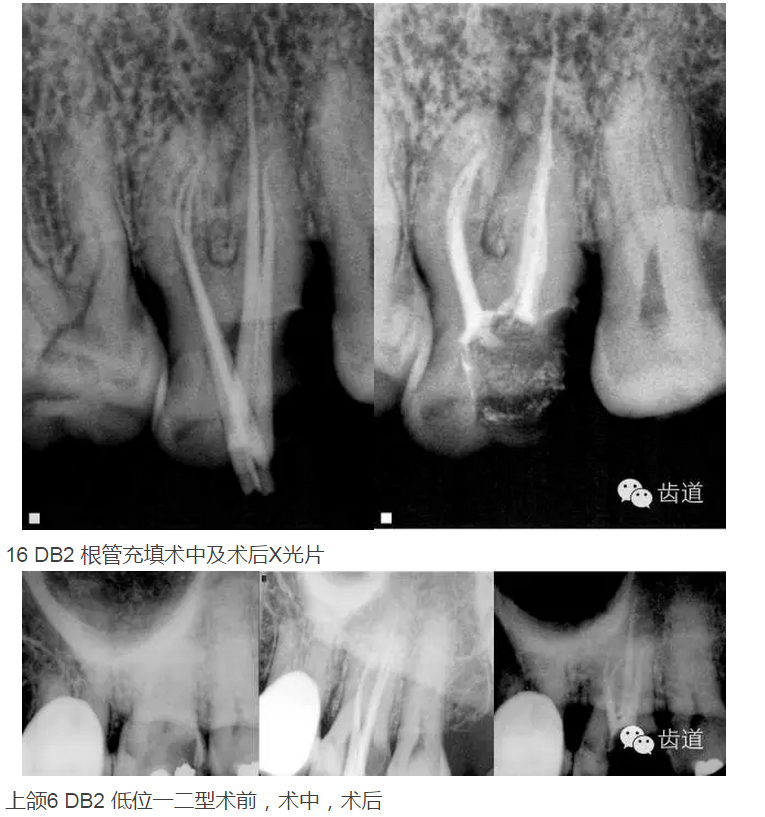

上頜第一磨牙:多為3-4個(gè)根管,MB2發(fā)生率約為60%;

上頜第二磨牙:與上頜第一磨牙相似,多為3根管,偶見雙鄂根管;